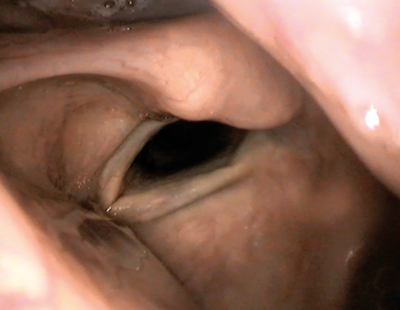

Approaching the vocal folds from above gives an excellent view of the tip of the needle as it enters the upper surface of the vocal fold (Figures 1-2).

Figure 1. Thyrohyoid approach for percutaneous medialisation injection.

Figure 2. Endoscopic view of medialisation injection via thyrohyoid approach;

note the progressive bulking of the right vocal fold as the material is injected.